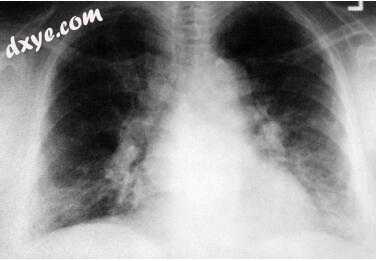

10.jpg

图-10. 双肺门淋巴结肿大和线性实质密度在56岁女性患有肺结节病。